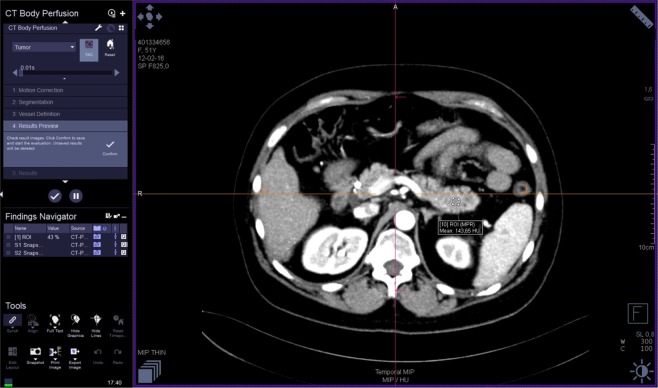

The images were analyzed by three radiologists (J.L.E. – reader 1, T.S.G. - reader 2, M.V. – reader 3) with 25, 16 and six years of experience in abdominal imaging, respectively. Each reader performed two reading sessions with at least a 24 h interval. The image data were processed on a workstation (Syngo.via®, Siemens) with commercial perfusion CT software (CT Body Perfusion, Siemens) based on the maximum slope model. Motion correction was performed by using a commercial non-rigid motion correction algorithm (Syngo®.via Body Perfusion, Siemens) to improve anatomical alignment. The following parameters were measured: blood flow (measured in mL/100 mL/min), blood volume (measured in mL/100 mL), time to peak (measured in seconds), and mean transit time (measured in seconds). Arterial input was measured by automatically placed ROI in the abdominal aorta. To obtain perfusion CT parameters, each radiologist manually drew three non-superposable circular ROI (between 1.0 and 2.0 cm²) in the head, three in the body and three in the tail of the pancreas to measure these parameters, avoiding visible vessels and ducts. The mean ROI value for each parameter in each part of the pancreas was considered for analysis. The parameters for the whole pancreas were calculated as the sum of the values of the pancreatic head, body and tail divided by three. An example of perfusion CT image processing is shown in Figs 1–3.

Figure 1.

Perfusion CT: image processing.